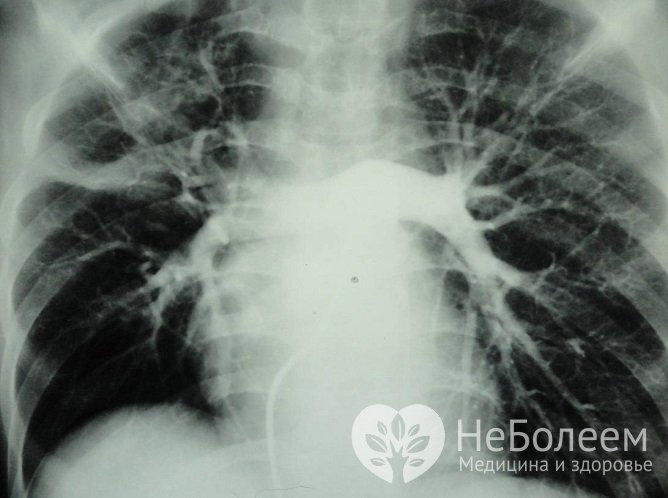

Существует несколько методов, которые применяются в клинике для измерения уровня давления в правых отделах сердца. Главные – инвазивный метод катетеризации сердца и неинвазивная эхокардиография. Катетеризация обеспечивает наиболее точный результат, но используется реже по причине связанных с ней рисков. Также проводится рентгенография органов грудной клетки, ЭКГ, спирометрия (дыхательные пробы).

Один из методов диагностики ЛГ – рентгенография грудной клетки Один из методов диагностики ЛГ – рентгенография грудной клетки